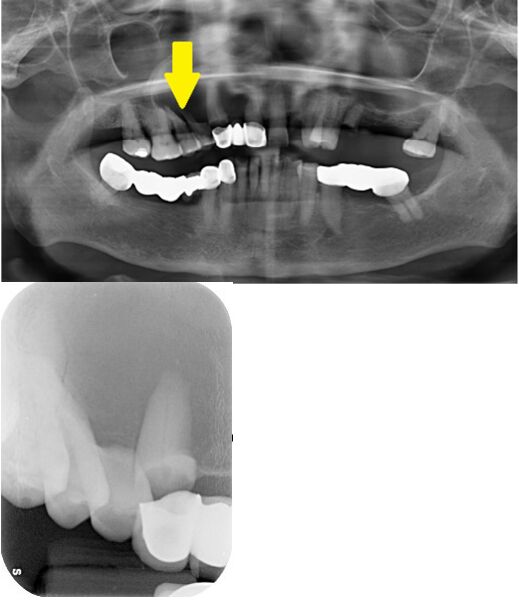

20.69歲女性,因為右側鼻翼區域腫脹就診。病人自述此腫脹出現約數月,其影像學檢查如圖所示。病人在接受手術移除病灶前,拔除右上犬齒與第一小臼齒時,有液體自拔牙後傷口流出。下列鑑別診 斷何者最不可能? (A)頰側雙叉囊腫(buccal bifurcation cyst) (B)單囊性造釉細胞瘤(unicystic ameloblastoma) (C)齒源性角化囊腫(odontogenic keratocyst) (D)根尖囊腫(periapical cyst)